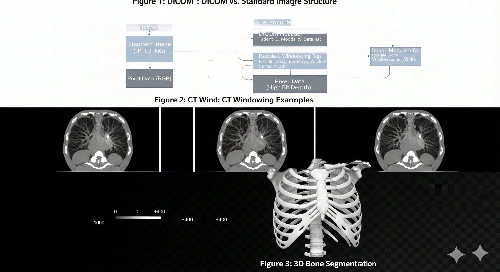

CT 영상의 가장 큰 특징은 픽셀 값이 **HU(Hounsfield Unit)**라는 절대 단위로 표현된다는 점입니다. 물은 0, 공기는 -1000, 뼈는 +400 이상의 값을 가집니다. 하지만 우리가 사용하는 모니터는 이 넓은 범위를 한 번에 보여주지 못합니다.

이때 필요한 것이 바로 **윈도잉(Windowing)**입니다. 분석하고자 하는 타겟(뼈, 장기, 폐 등)에 맞춰 특정 범위의 HU 값만 강조하여 시각화하는 과정입니다.

- Window Level (WL): 보고자 하는 중심값

- Window Width (WW): 보여줄 범위의 너비

5. 데이터 세분화(Segmentation): 특정 장기 추출하기

전처리가 완료된 데이터에서 특정 임계값(Thresholding)을 적용하여 뼈 조직만 추출하거나, 마스크(Mask) 이미지를 생성하는 과정입니다.